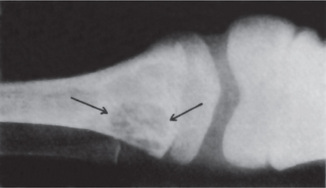

The teeth present a unique appearance characterized by the absence of cementum, presumably as a result of failure of cementogenesis, so that there is no sound functional attachment of the tooth to bone by periodontal ligament (Fig. 15-10). This lack of attachment is thought to account for the early spontaneous exfoliation of the deciduous teeth. Occasional foci of poorly formed cementum may be found on some teeth.

Figure 15-10 Hypophosphatasia.

A maxillary deciduous incisor of a patient with hypophosphatasia which was exfoliated at 15 months of age (A). The tooth root showed only a poor attempt at cementogenesis indicated by the granular, basophilic material between the dentin on the left and the periodontal fibers on the right (B) Courtesy of Dr Robert J Bruckner.